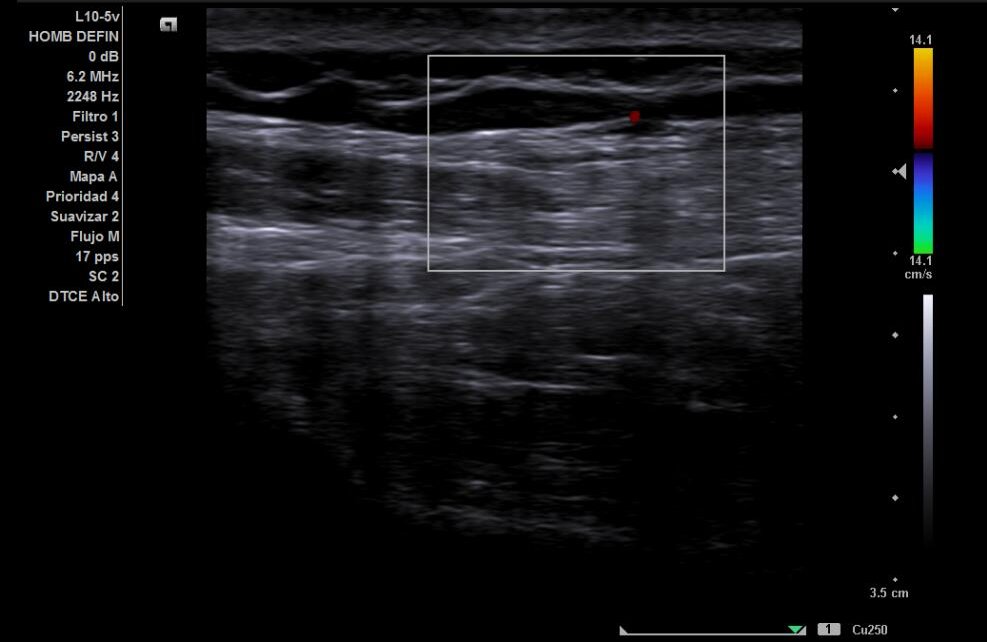

Hallazgos ecográficos

Tendones supra e infraespinoso normales; bursa fina; cabeza larga del bíceps normal. Nervio supraescapular discretamente hipoecoico y engrosado en la escotadura; sin colecciones. Sin signos de pinzamiento dinámico.